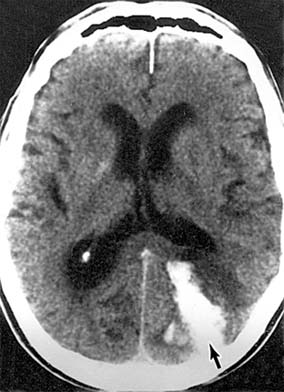

Lesions involving the geniculocalcarine pathway to the occipital cortex produce homonymous field defects but do not result in optic atrophy (due to the synapse at the geniculate nucleus). Generally, the more posterior a lesion is located, the more congruous the homonymous visual field defect. The inferior geniculocalcarine pathway passes through the temporal lobe and the superior pathway through the parietal lobe, with macular function between them. Lesions of the inferior pathway result in superior visual field defects. Processes affecting the anterior and midtemporal lobes are commonly neoplastic; posterior temporal lobe and parietal processes can be either vascular or neoplastic. An insidious onset with mild and multiple neurologic deficits would be more typically neoplastic, whereas an acute cataclysmic neurologic event would be more typically vascular. Vascular lesions of the occipital lobe, on the other hand, are common and account for over 80% of cases of isolated homonymous visual field loss in patients over age 50 years. The most posterior tip of each occipital lobe projects to homonymous macular fields. Anterior to the macular representation lies the peripheral field; thus, vascular occlusions can selectively involve the posterior occipital cortex and produce homonymous defects with congruous macular scotomas or spare the posterior cortex, and homonymous defects with macular sparing will result. The cortical centers involved in the generation of optokinetic nystagmus lie in the area between the occipital and temporal lobes and in the posterior parietal area, which are within the vascular territory of the middle cerebral artery. Optokinetic nystagmus asymmetry characteristically occurs in parietal lesions but not in occipital lesions. An asymmetric optokinetic nystagmus combined with an occipital visual field defect indicates a process not respecting vascular territories and thus suggests a tumor (Cogan's sign). CT scans and MRI demonstrate cerebral lesions with remarkable clarity (Figures 14-4, 14-5, 14-28, and 14-29).

Figure 14-28

Figure 14-28: Occipital hematoma (arrow) resulting from a bleeding arteriovenous malformation. This lesion produced homonymous hemianopia and headache.